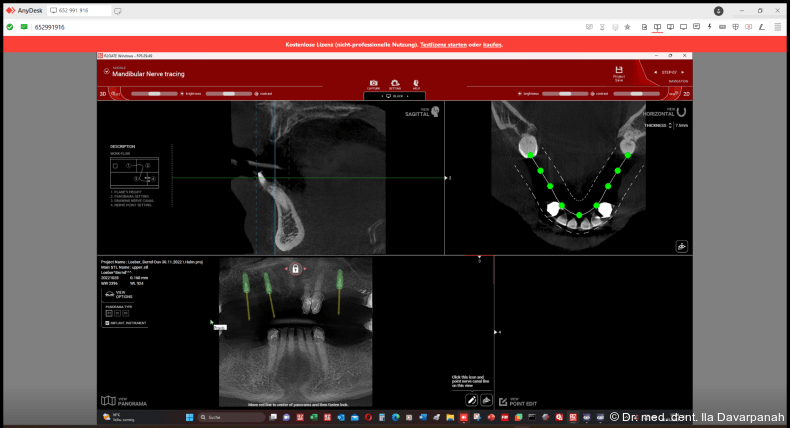

Die virtuelle Implantatplanung erfolgte nach dem Backward Planning-Prinzip. Hierzu wurden ein DVT des Schädels als Dicom-Datensatz sowie ein intraoraler Scan (Medit i700, Medit) als STL-Datensatz erstellt und für eine dreidimensionale Planung in der Planungssoftware R2Gate (MegaGen Implant Co.) importiert (Abb. 3+4). Hierfür ist eine sorgfältige Abstimmung von Datenerfassung, Planung und Fertigung wichtig. Nach Überlagerung der Daten werden die idealen prothetischen und anatomischen Vorgaben bestimmt.